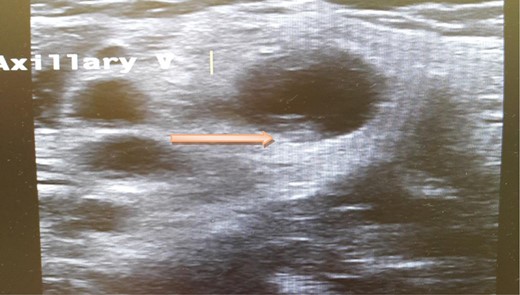

A computed tomography scan of the chest, abdomen and pelvis revealed splenic vein thrombosis (Fig. 1); and a filling defect in the lower lobar segmental branch of the right pulmonary artery consistent with acute segmental pulmonary embolism. A venous duplex scan of the extremities showed thrombosis of the left axillary and basilic veins (Figs 2 and 3). Echocardiogram was normal.

Ultrasound scan of the basilic vein with evidence of thrombus formation.